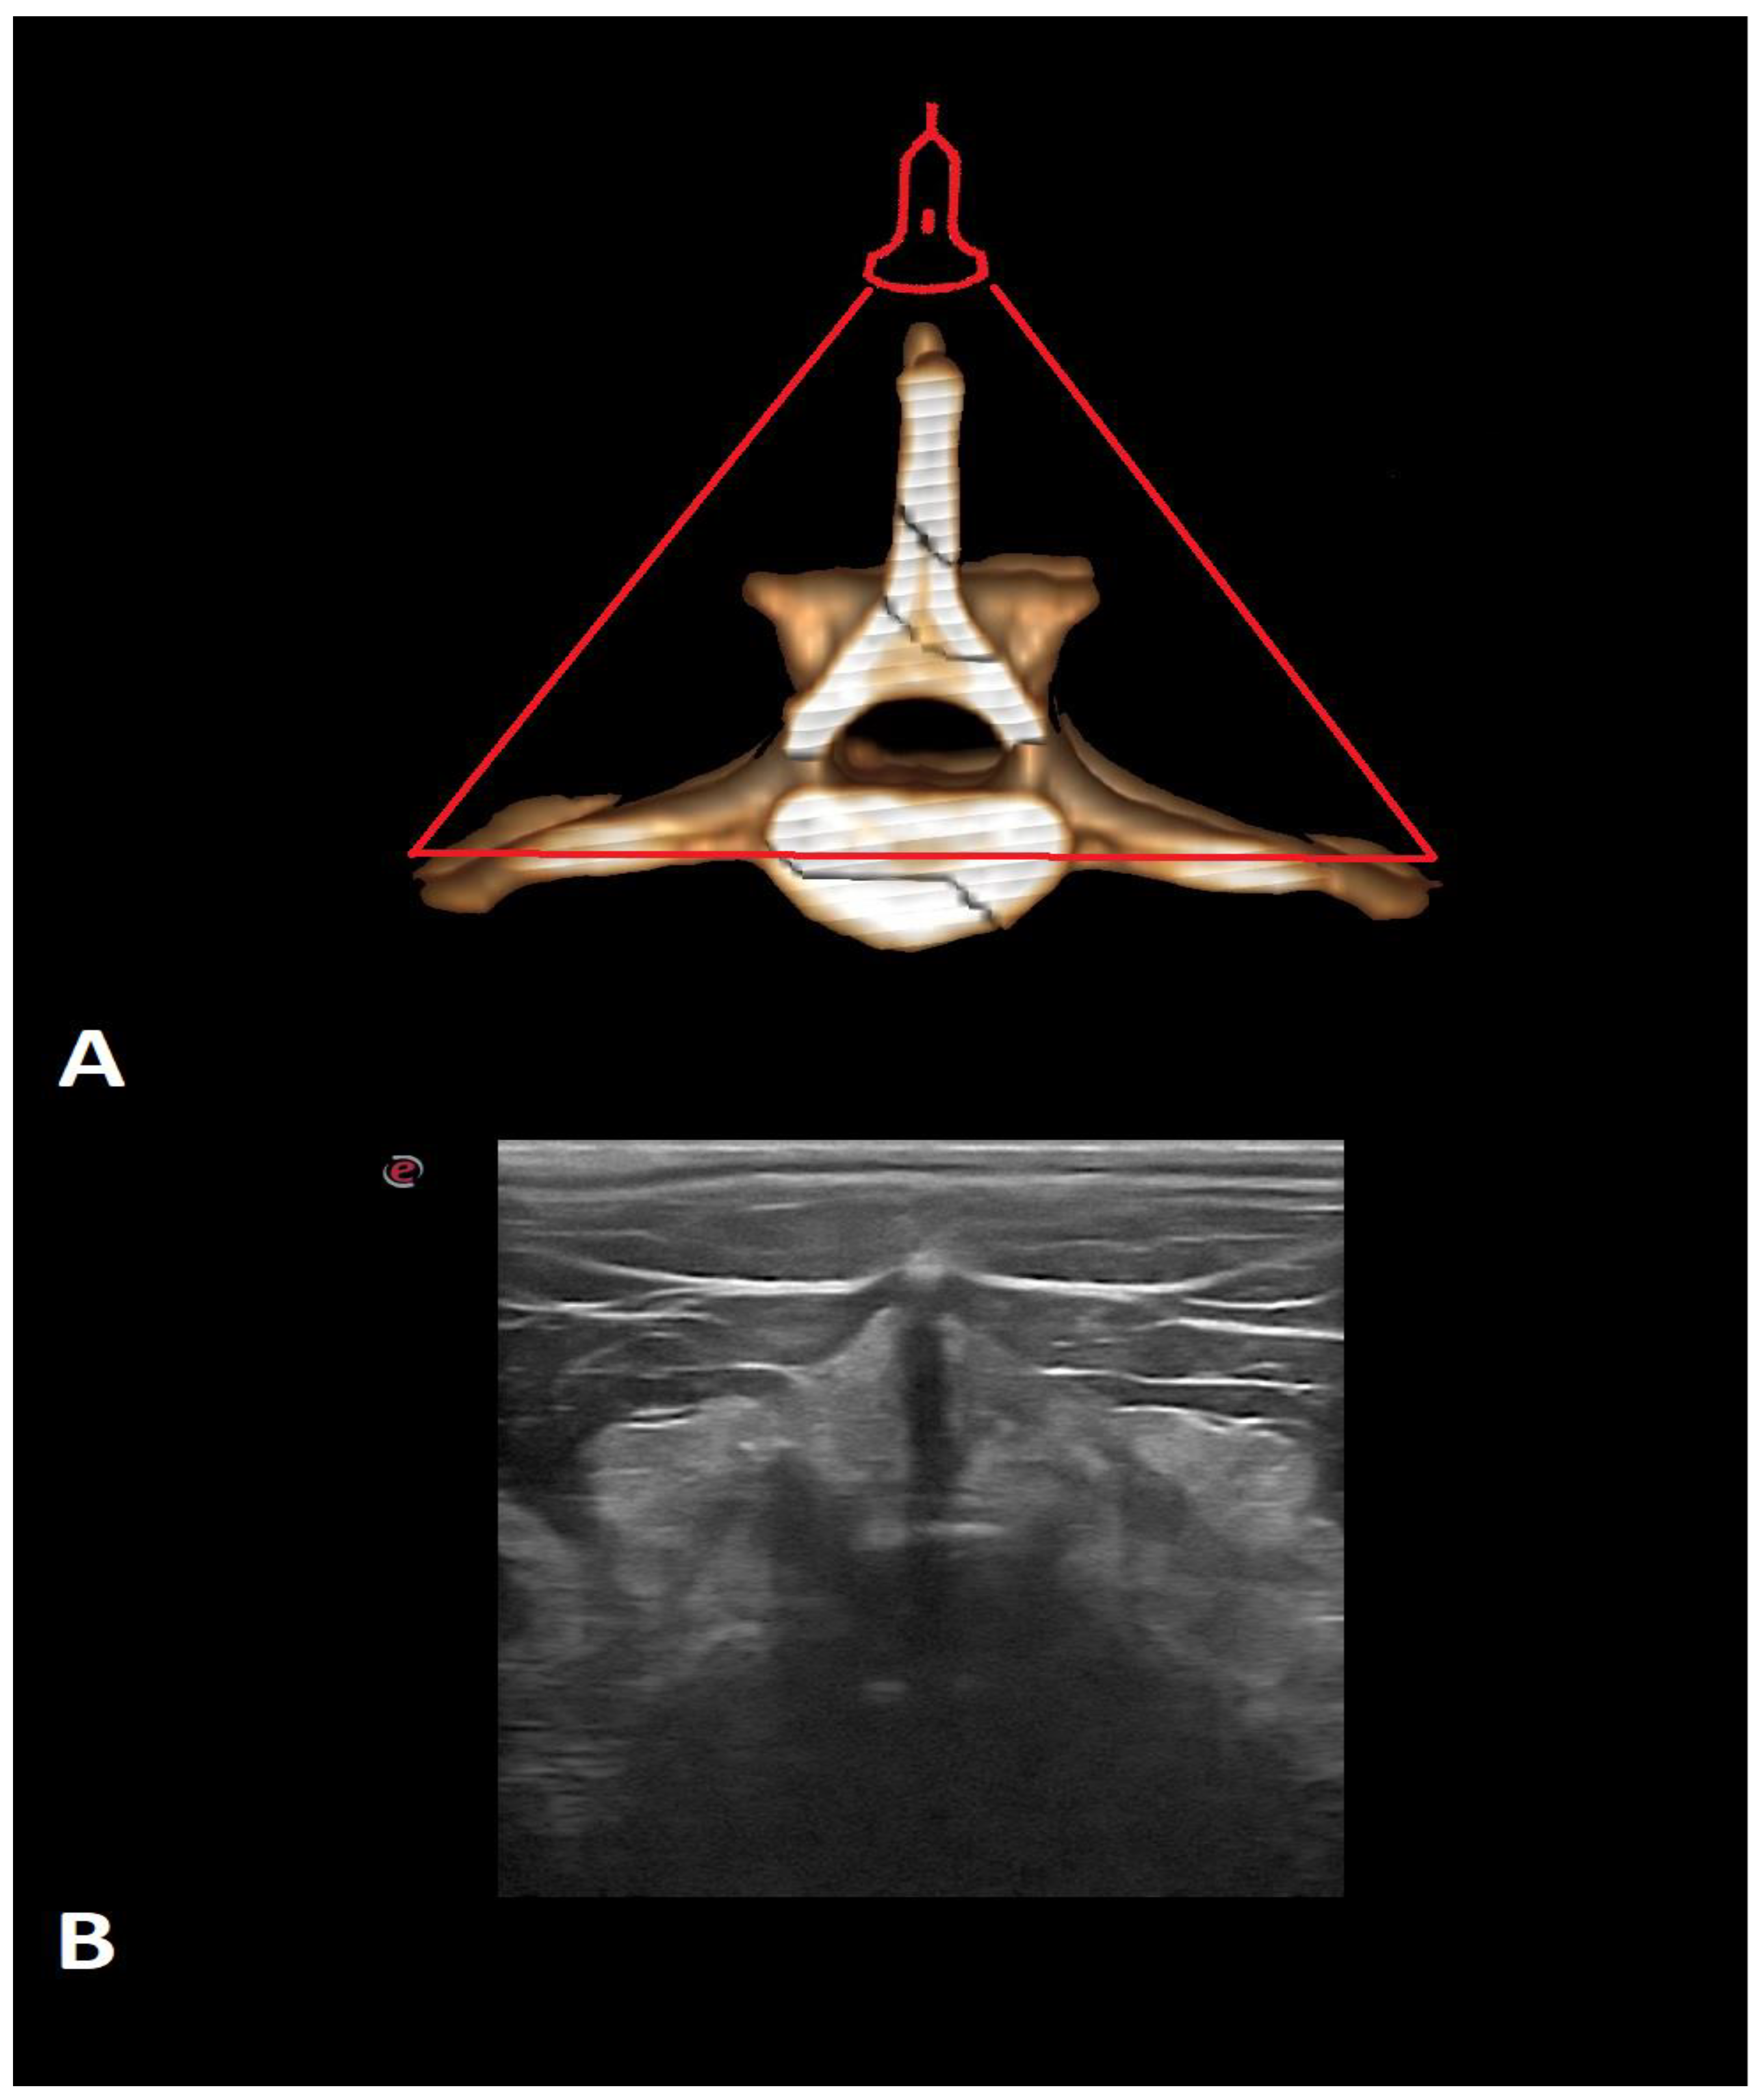

- Lopes, É.R.; Bellegard, G.M.; Cury, F.S.; Abreu, F.A.; Ambrósio, C.E.; Carregaro, A.B.; Hage, M.C.F. Evaluation of the applicability of musculoskeletal ultrasonography of the thoracolumbar and lumbar spine segment of healthy dogs. Pesqui. Veterinária Bras. 2018, 38, 2278–2283. [Google Scholar] [CrossRef]